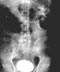

Bony structures of the pelvis Observe the peritoneal relationships in the pelvis and identify the rectum. Notice how these structures and the associated peritoneum form the rectouterine and vesicouterine pouches in the female and rectovesical pouch in the male.

3. Remove the peritoneal covering of the bladder and examine. (Play movie; View images: N 360, 361, 362, 366, 402, 403, 406, 407, 408, 410, TG 6-07A, 6-07B, 6-08A, 6-08B, 6-10A, 6-10B, 6-17A, 6-17B, 6-19A, 6-19B, 6-33, 6-34)

Urinary bladder: Observe peritoneal coverings of the urinary bladder. Note the different reflection in male and female. Remove the peritoneum and identify the urachus (median umbilical ligament). Examine the musculature of the bladder wall and identify the ureteric orifices, the interureteric crest, the urethral orifice, and the trigone. In the male look for a uvula. Blood supply, innervation and lymphatic drainage of the bladder will be exposed in a later dissection.